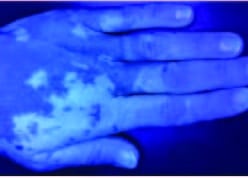

Einführung in hypopigmentierte Flecken:

- Hypopigmentierte Flecken treten auf, wenn pigmentproduzierende Zellen (Melanozyten) absterben oder die Produktion von Melanin einstellen.

- Die betroffenen Hautflecken werden heller oder weißer. Es ist unklar, was genau diese Pigmentzellen zum Versagen oder Absterben bringt.